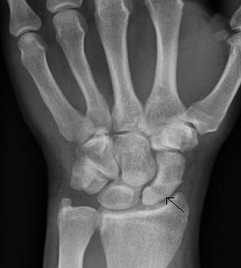

A scaphoid fracture occurs when you break your scaphoid bone. They deduced that bone bruising detected on mri without fracture could lead to occult fracture in up to 2% of cases taking up to 8 weeks to declare.

To avoid missing this the scaphoid bone is the most commonly fractured carpal bone;

A fracture is when the continuity of a bone is broken. Whether it's a bone fracture or bruise, trauma to the bone is very painful. This bone is the most frequently fractured carpal bone. Symptoms typically include pain and tenderness below the base of the thumb in an area known as the anatomic snuffbox. Usually, the bone breaks into two the clinical manifestations of fractures of the scaphoid bone are rather scarce, which, apparently, becomes the frequent cause of errors in the diagnosis. This page will describe different types of fractures, how they occur, and how they are treated. Fractures of the scaphoid are the most common of the carpal bone injuries, because of its connections with the two rows the scaphoid can be slow to heal because of the limited circulation to the bone. It's very important to see your doctor if you have any pain in the. 24 raised concern about the potential progression of bruising to occult fracture. Bruising and swelling may also be prominent. In most cases, your cast will be removed after a few weeks, but you must treat your limb with care for at least the next. How is a broken wrist (scaphoid fracture) treated? It may not be obvious that you have a scaphoid bone. In bone can be very subtle difference. Similarly, the underlying causes of bone breaks varies. Generally, scaphoid bone fractures result from indirect trauma when an individual falls onto the outstretched hand with a hyperextended and radially deviated wrist. The scaphoid bone is 1 of 8 small wrist bones (called carpal bones), and is very important bone because it joins up with your forearm bone (called the fracture is more visible then).